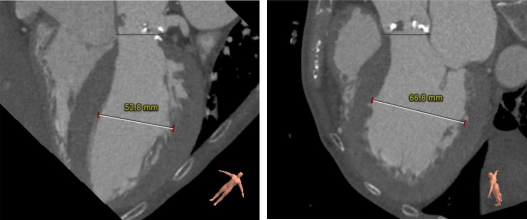

Annulus:26.3 mm

LVOT:28.3 mm

SOV:35.0*30.7*37.2 mm(L*R*N)

STJ:33.2 mm

Above 40 mm:44.6mm

Ascending Aorta Max:47.5 mm

Height(R): 12.8 mm

Height(L): 6.7 mm